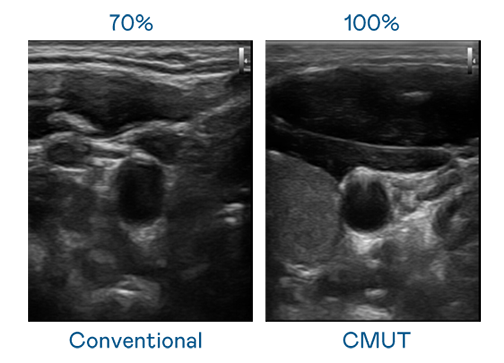

CMUT 技术是一种用电容式微机电元件来产生超音波讯号的技术。与传统 PZT 压电式技术相比,CMUT 频宽增加 30%,更宽频的超音波讯号让影像解析度大幅提升,是实现高影像品质医疗超音波扫描、促进精准医疗发展的关键技术。

超音波影像的解析度高低,首先取决于探头能发出的讯号频宽。BG视讯 CMUT 可提供高清晰的超音波讯号,提供高频宽、高灵敏度、影像纹理细节更高的超音波影像,协助医护人员缩短影像判读时间及利用精准的医疗影像进行诊断。